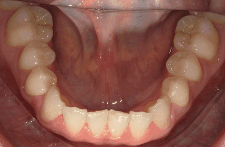

Diganosis: Moderate lower anterior crowding, square and narrow maxilla, rotated #19

Adjuncts: Attachments

Initial treatment

INTRAORAL